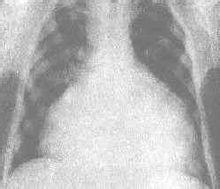

燒瓶心,所說的是X線胸片上,心影呈燒瓶樣球形擴張,雙側心室增大圓隆,下大上小類似燒瓶,這是心包積液的特徵性表現。